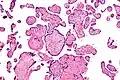

VUE can be of 2 types, low grade chronic villitis or high grade chronic villitis. Low grade chronic villitis involves less than 10 villi containing lymphocytes. Low grade chronic villitis can be either focal or multifocal. Focal has involved villi on only one glass slide, while multifocal has involved villi on at least two slides. High grade chronic villitis has more than 10 inflamed villi per focus. High grade chronic villitis is differentiated into diffuse and patchy. The term patchy is used if less than 30% of distal villi are involved. The term diffuse is used if more than 30% of distal villi are involved.

VUE has 2 prominent distinct patterns. Approximately 50% of the cases only involve the distal villi (mature intermediate and terminal villi) and do not involve the proximal stem villi, the anchoring villi embedded in the basal plate, and the chorionic plate. The second most common pattern (roughly 30% of VUE cases) involves the proximal stem villi (and possibly the chorionic plate) and the distal villi usually. This type of VUE is linked with foetal vascular obtrusive lesions (Obliterative Foetal Vasculopathy).[1][16]

VUE does not have specific clinical signs and symptoms suggesting diagnosis; but an analysis of the inflammatory filtrate can aid in diagnosis.[1] The composition of inflammatory infiltrate in VUE on a cellular level is primarily macrophages and lymphocytes. The relative proportions of cells vary case by case. The lymphocytes present in VUE are predominantly CD8+ T-cells then CD4. There is usually a ratio of 0.1 to 0.5 for CD4/CD8.[17][18] The macrophages present are mainly Mac387-, followed by CD68 and HAM56+. Class 2 major histocompatibility complex (MHC) antigens on macrophages are up-regulated at sites of VUE. Neutrophils should not be present at sites of VUE. VUE is a condition involving inflammation and not infection. High numbers of neutrophils are present in infectious villitis and not VUE.[1][14]

Histomorphologically, VUE is characterized by a lymphocytic infiltrate of the chorionic villi without a demonstrable cause. Plasma cells should be absent; the presence of plasma cells suggests an infective etiology, e.g. CMV infection.